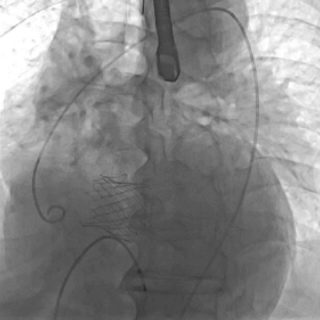

截止目前,臨床試驗進展順利,入組已接近尾聲。中期分析顯示手術成功率和安全性指標均符合預期標準。

瓣膜功能、形態良好,未見反流